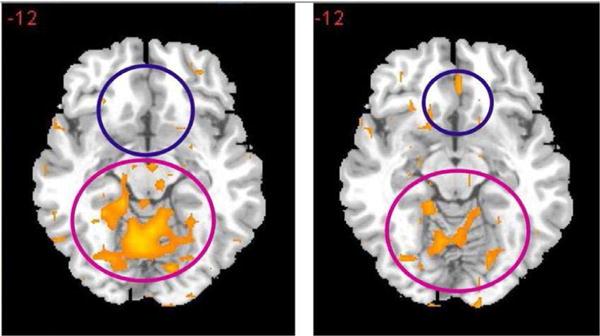

We are faced with a worldwide opiate/opioid epidemic that is devastating. According to the Centers for Disease Control and Prevention (CDC), at least 127 people, young and old, are dying every day in America due to narcotic overdose. The Food and Drug Administration (FDA) has approved Medication-Assisted Treatments (MATs) for opiate/opioids as well as alcohol and nicotine. The mechanism of action of most MATS favors either blocking of dopaminergic function or a form of Opiate Substitution Therapy (OST). These treatment options are adequate for short-term treatment of the symptoms of addiction and harm reduction but fail long-term to deal with the cause or lead to recovery. There is a need to continue to seek better treatment options. This mini-review is the history of the development of one such treatment; a glutaminergic-dopaminergic optimization complex called KB220. Growing evidence indicates that brain reward circuitry controls drug addiction, in conjunction with "anti-reward systems" as the "anti-reward systems" can be affected by both glutaminergic and dopaminergic transmission. KB220 may likely alter the function of these regions and provide for the possible eventual balancing the brain reward system and the induction of "dopamine homeostasis." Many of these concepts have been reported elsewhere and have become an integral part of the addiction science literature. However, the concise review may encourage readership to reconsider these facts and stimulate further research focused on the impact that the induction of "dopamine homeostasis" may have on recovery and relapse prevention.

我们正面临一场全球性的阿片类药物流行,其破坏性极大。根据疾病控制与预防中心(CDC)的数据,在美国,每天至少有127人,无论老少,死于麻醉品过量。美国食品药品监督管理局(FDA)已批准用于阿片类药物以及酒精和尼古丁的药物辅助治疗(MATs)。大多数MATs的作用机制有利于阻断多巴胺能功能或采用某种形式的阿片类药物替代疗法(OST)。这些治疗方案对于成瘾症状的短期治疗和减少伤害是足够的,但长期来看无法解决成瘾的根源或实现康复。因此,有必要继续寻找更好的治疗方案。这篇小型综述讲述的是一种这样的治疗方法的发展历程;一种名为KB220的谷氨酰胺能 - 多巴胺能优化复合物。越来越多的证据表明,大脑奖赏回路与“反奖赏系统”共同控制药物成瘾,因为“反奖赏系统”会受到谷氨酰胺能和多巴胺能传递的影响。KB220可能会改变这些区域的功能,并有可能最终实现大脑奖赏系统的平衡以及诱导“多巴胺稳态”。其中许多概念在其他地方已有报道,并已成为成瘾科学文献的重要组成部分。然而,这篇简要综述可能会促使读者重新审视这些事实,并激发进一步的研究,聚焦于“多巴胺稳态”的诱导对康复和预防复发可能产生的影响。